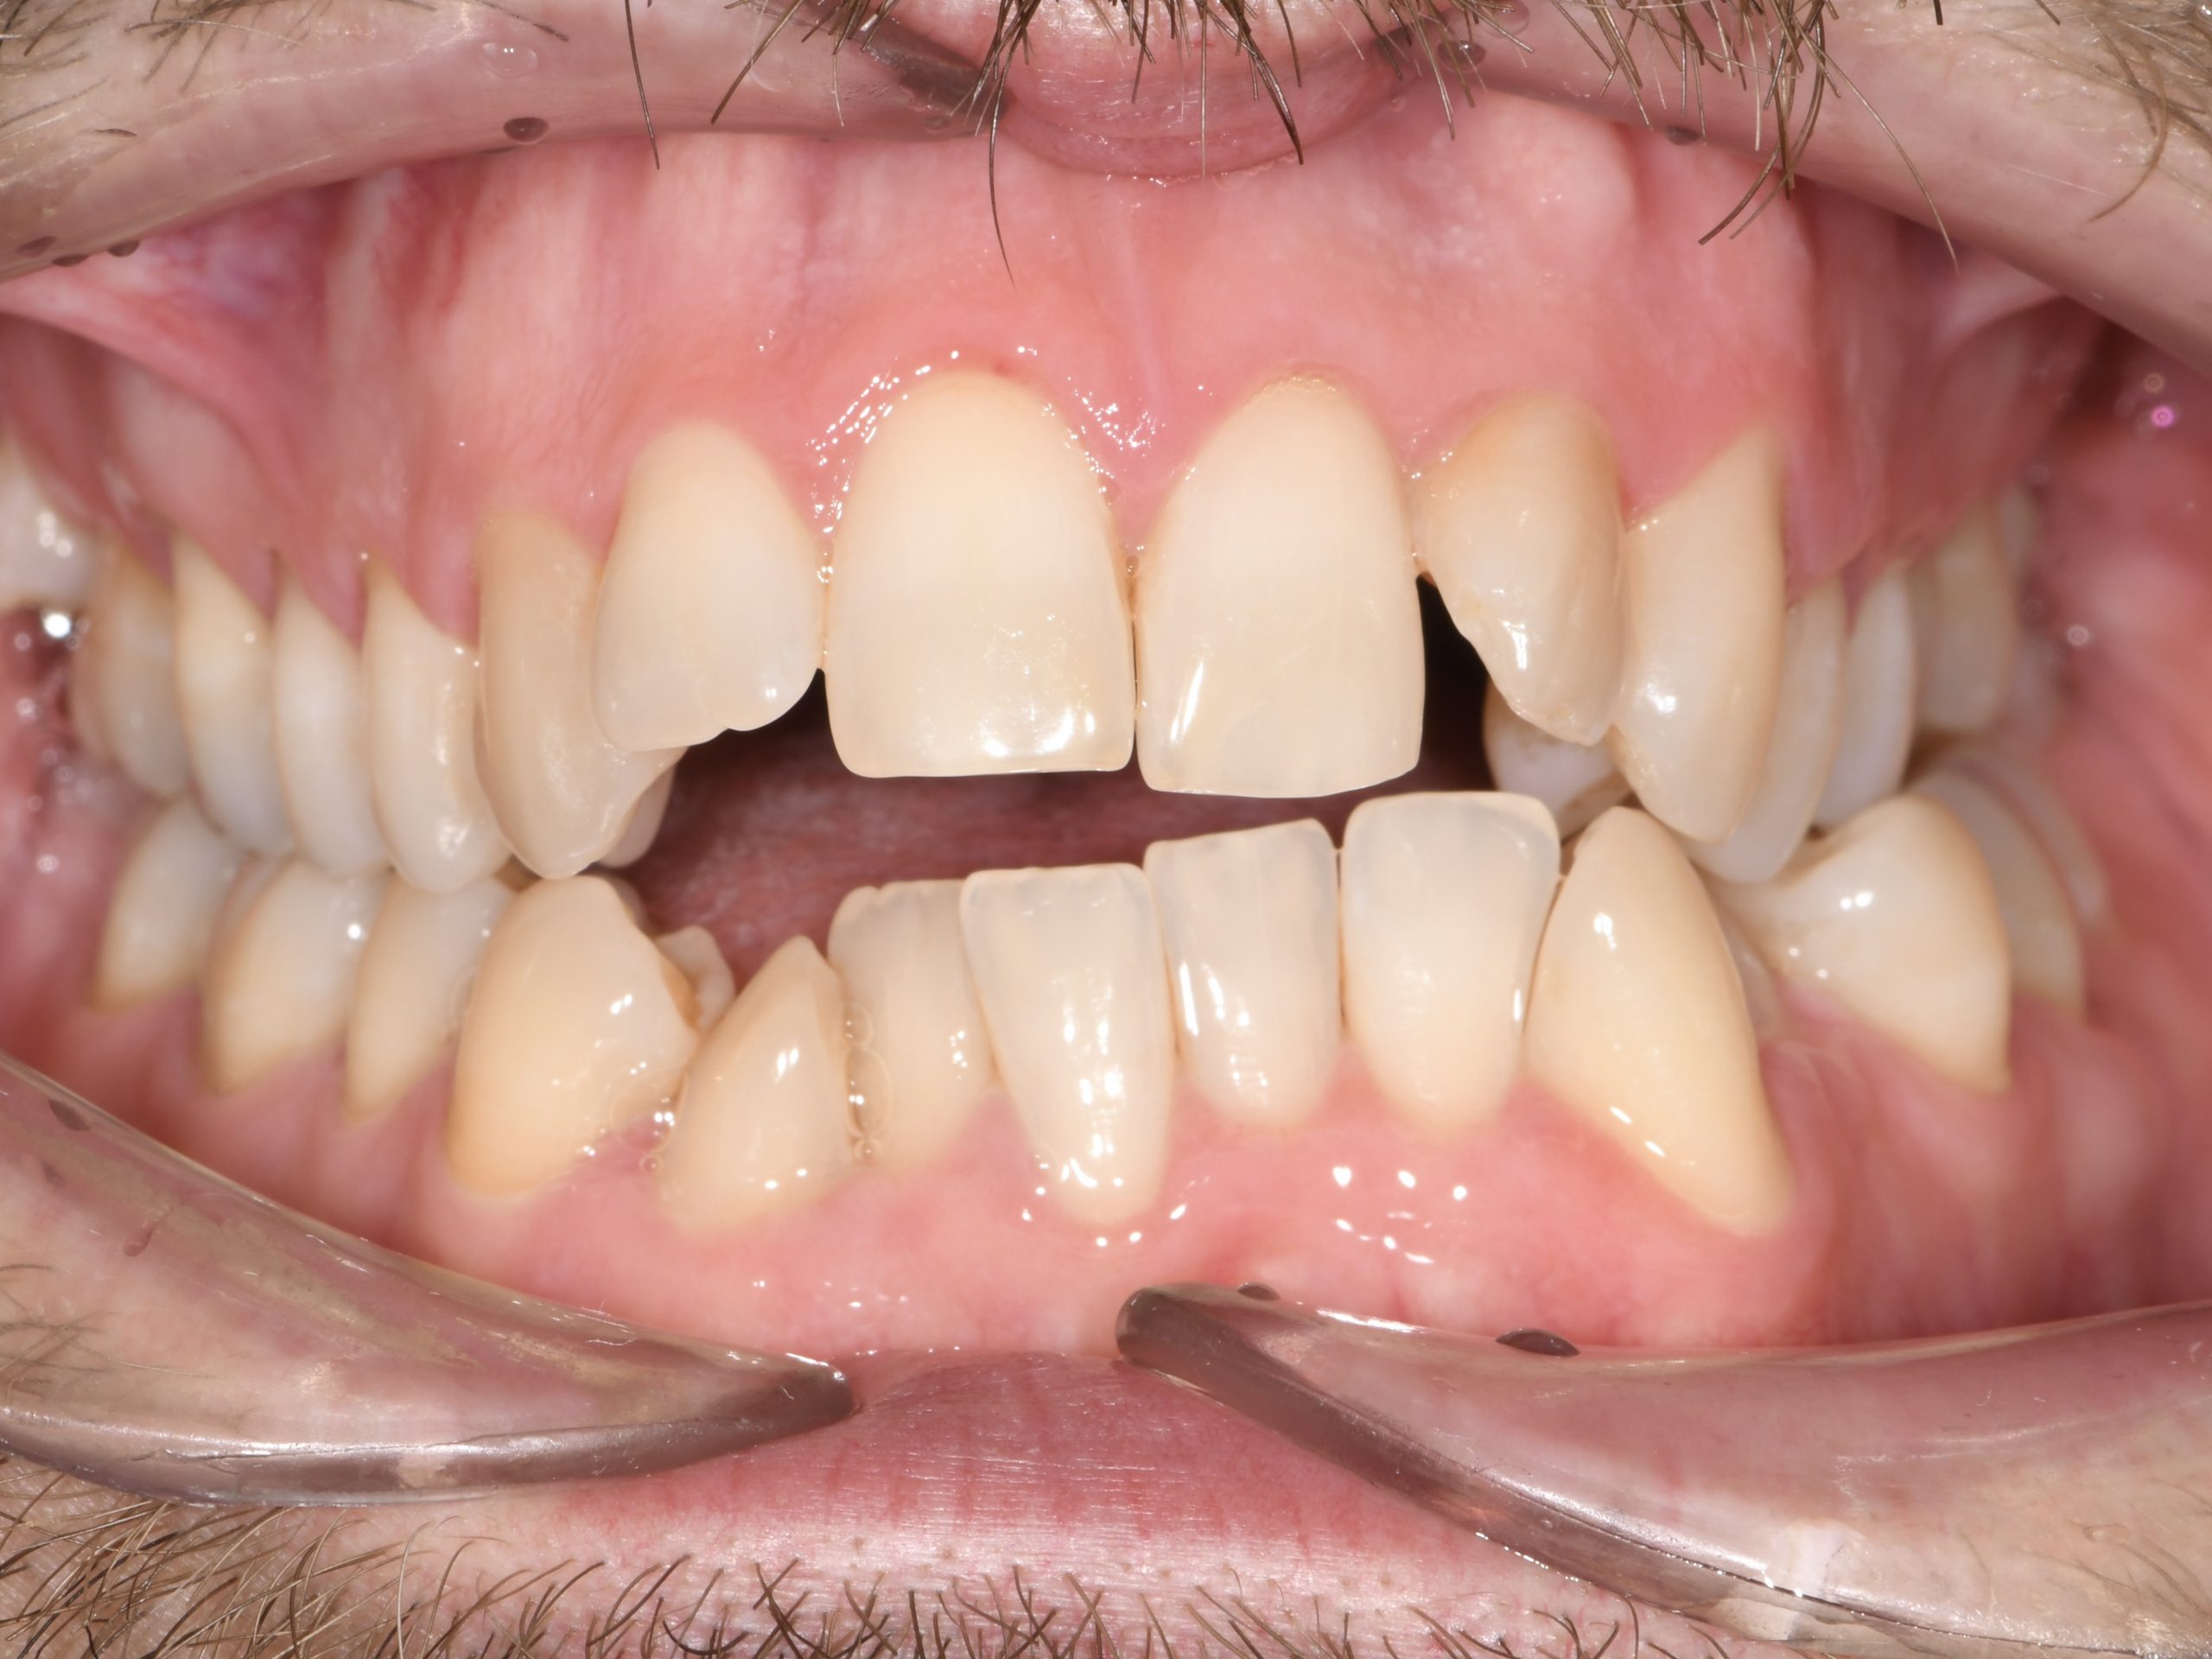

Az elmúlt évekből rengeteg szakmai referenciát tudnánk bemutatni, amelyek különböző fogszabályozási problémákat oldottak meg. Válogatva a több száz esetből, ezen az oldalon olyan képeket, információkat igyekeztünk bemutatni, amelyeknek a segítségével a jövőbeni pácienseinknek azt tudjuk üzenni: A Te fogsorod is lehet gyönyörű!

(Képeket a Pácienseink külön írásos beleegyezésével mutatjuk be!)